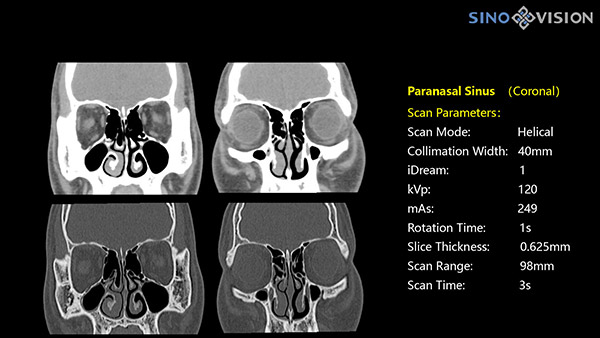

Компьютерные томографы SinoVision обеспечивают удобное размещение пациентов, превосходную визуализацию структур, включая мелкие сосуды, и низкую лучевую нагрузку.

- Высокое разрешение

Подходят для решения сложных задач общей диагностики, хирургии, сосудистой визуализации, моделирования и биопсии при онкологии.

Программное обеспечение на базе ИИ позволяет проводить постобработку с использованием облачных хранилищ и технологий удалённой диагностики, оценку морфологии, качественный анализ с помощью технологии спектральной визуализации.

Подходит для большинства рутинных и углубленных специализированных исследований, в том числе педиатрических и кардиологических исследованиях при сверхнизких дозах.